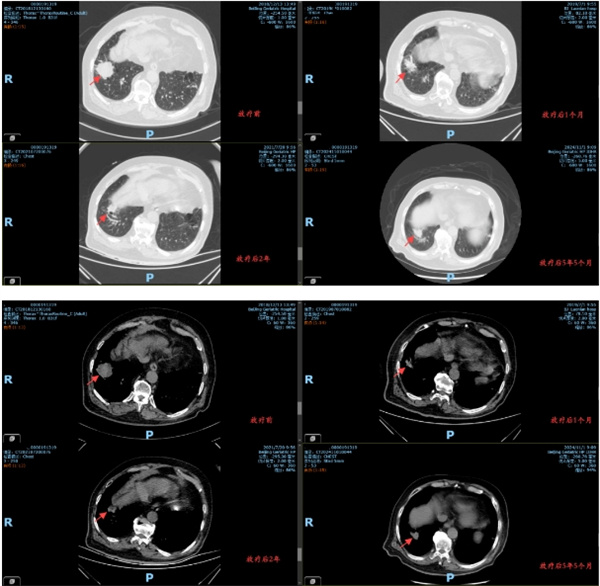

从2019年4月至5月,李大爷接受了共30次精准放疗。治疗过程顺利,期间无明显不良反应。放疗团队通过实时影像引导技术,确保每次治疗都精准靶向病灶区域,力求既达到局部控制效果,又避免损伤周围正常组织。

放疗后的复查显示,李大爷右肺下叶的病灶明显缩小,血氧水平得到改善,身体状况显著提升。更令人欣慰的是,自2019年以来,李大爷的病灶未再出现进展,五年随访中始终保持稳定。